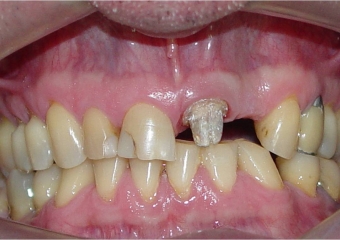

Imagens iniciais, mostrando ausência do elemento 22

Imagem inicial